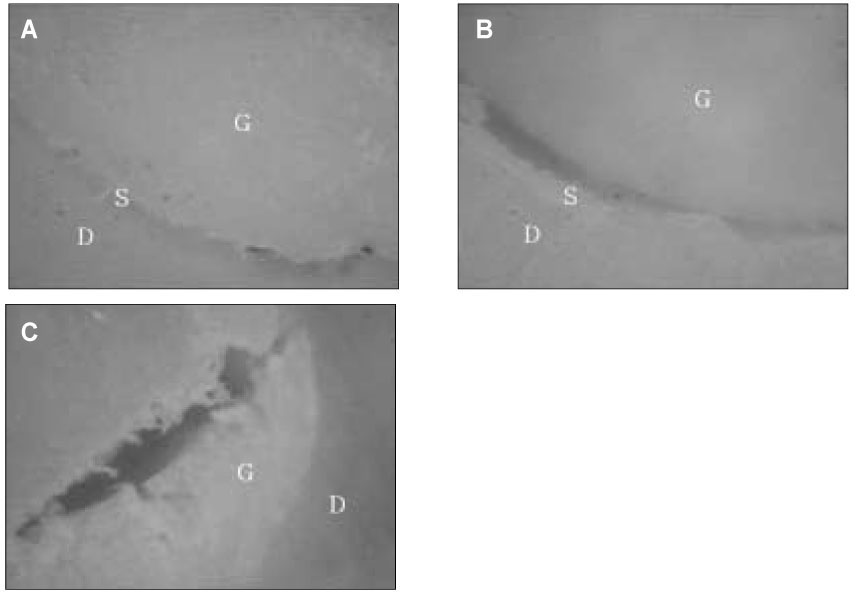

In the failure pattern analysis, there was no cohesive failure in Group G1, G2, and R1. Gutta-percha/AH 26 sealer groups appeared to exhibit predominantly adhesive and mixed failure patterns, whereas Resilon/Epiphany sealer groups exhibited mixed failures with the cohesive failure occurred within the Resilon substrate.